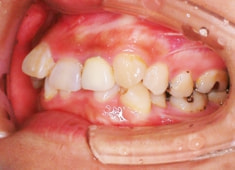

治療開始から1年8ヶ月後